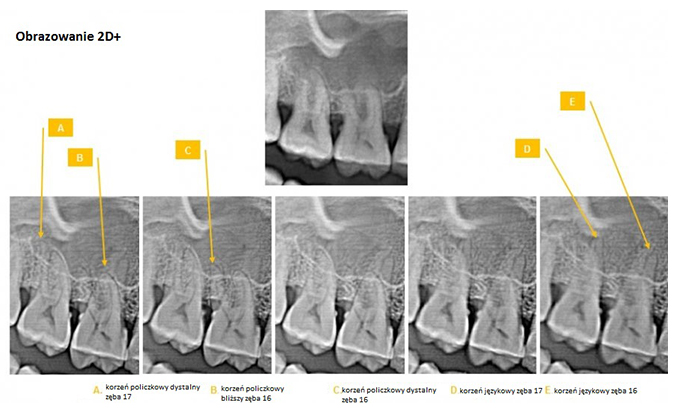

Zdjęcie panoramiczne zębów 2D+. Alternatywa dla tomografii. Nowe możliwości w RTG zębów!

W niektórych przypadkach istnieje możliwość lokalizacji zmiany bez konieczności wykonywania tomografii co znacząco obniża koszty leczenia.

Technologia 2D+

Ekskluzywny program tomosyntezy 2D+ kreuje cienkie slajdy, dzięki którym można pozyskać więcej diagnostycznych informacji na temat lokalizacji struktur niż daje standardowe zdjęcie panoramiczne zębów.

- kilka sekwencji jednej lokalizacji i stworzenie serii cienkich slajdów w regularnych odstępach szczęki różniących się ostrością uwidocznionych struktur umożliwia ocenę położenia względem siebie struktur anatomicznych

- pantomograf wykonuje slajdy od strony policzkowej w kierunku języka

- pantomografia 2D+ pozwala określić zęby zatrzymane, korzenie podniebienne lub identyfikować kanał nerwu zębodołowego

W efekcie rentgen zębów nie zostaje przedstawiony w postaci klasycznego zdjęcia panoramicznego zębów, a w postaci kolejnych sekwencji RTG zębów.